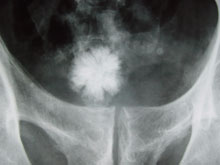

En revanche, les choses se compliquent dès lors que l'ingestion se fait de façon récurrente. Après plusieurs semaines avec 1 500 mg de mélamine par kilo et par jour, les rats (surtout les mâles) présentent des dysfonctionnements rénaux et urinaires : réactions inflammatoires, hyperplasie de la vessie et formations de calculs rénaux*. De plus, ces « cailloux » – des cristaux de mélamine et de l'un de ses métabolites, l'acide cyanurique – ne se comportent pas comme des calculs classiques. En 2007, des chercheurs de l'université du Michigan ont montré que, chez les animaux empoisonnés à la mélamine, les cristaux ne se dissolvaient pas normalement. Ils étaient plus lents à se résorber, ce qui laissait entrevoir une toxicité potentiellement chronique de la substance.

A cette question, les instances internationales n'ont qu'une réponse très partielle. Le plus important taux de mélamine découvert dans la poudre de lait chinois est d'environ 2 563 mg/kg avec une valeur médiane pour l'ensemble des échantillons épinglés de 29 mg/kg. Un calcul rapide montre qu'un nourrisson qui n'aurait été nourri qu'avec le lait le plus hautement contaminé au cours des six premiers mois de sa vie a en fait, ingurgité entre 600 mg et 725 mg de mélamine par jour (soit environ entre 200 mg/kg/jour et 145 mg/kg/jour).